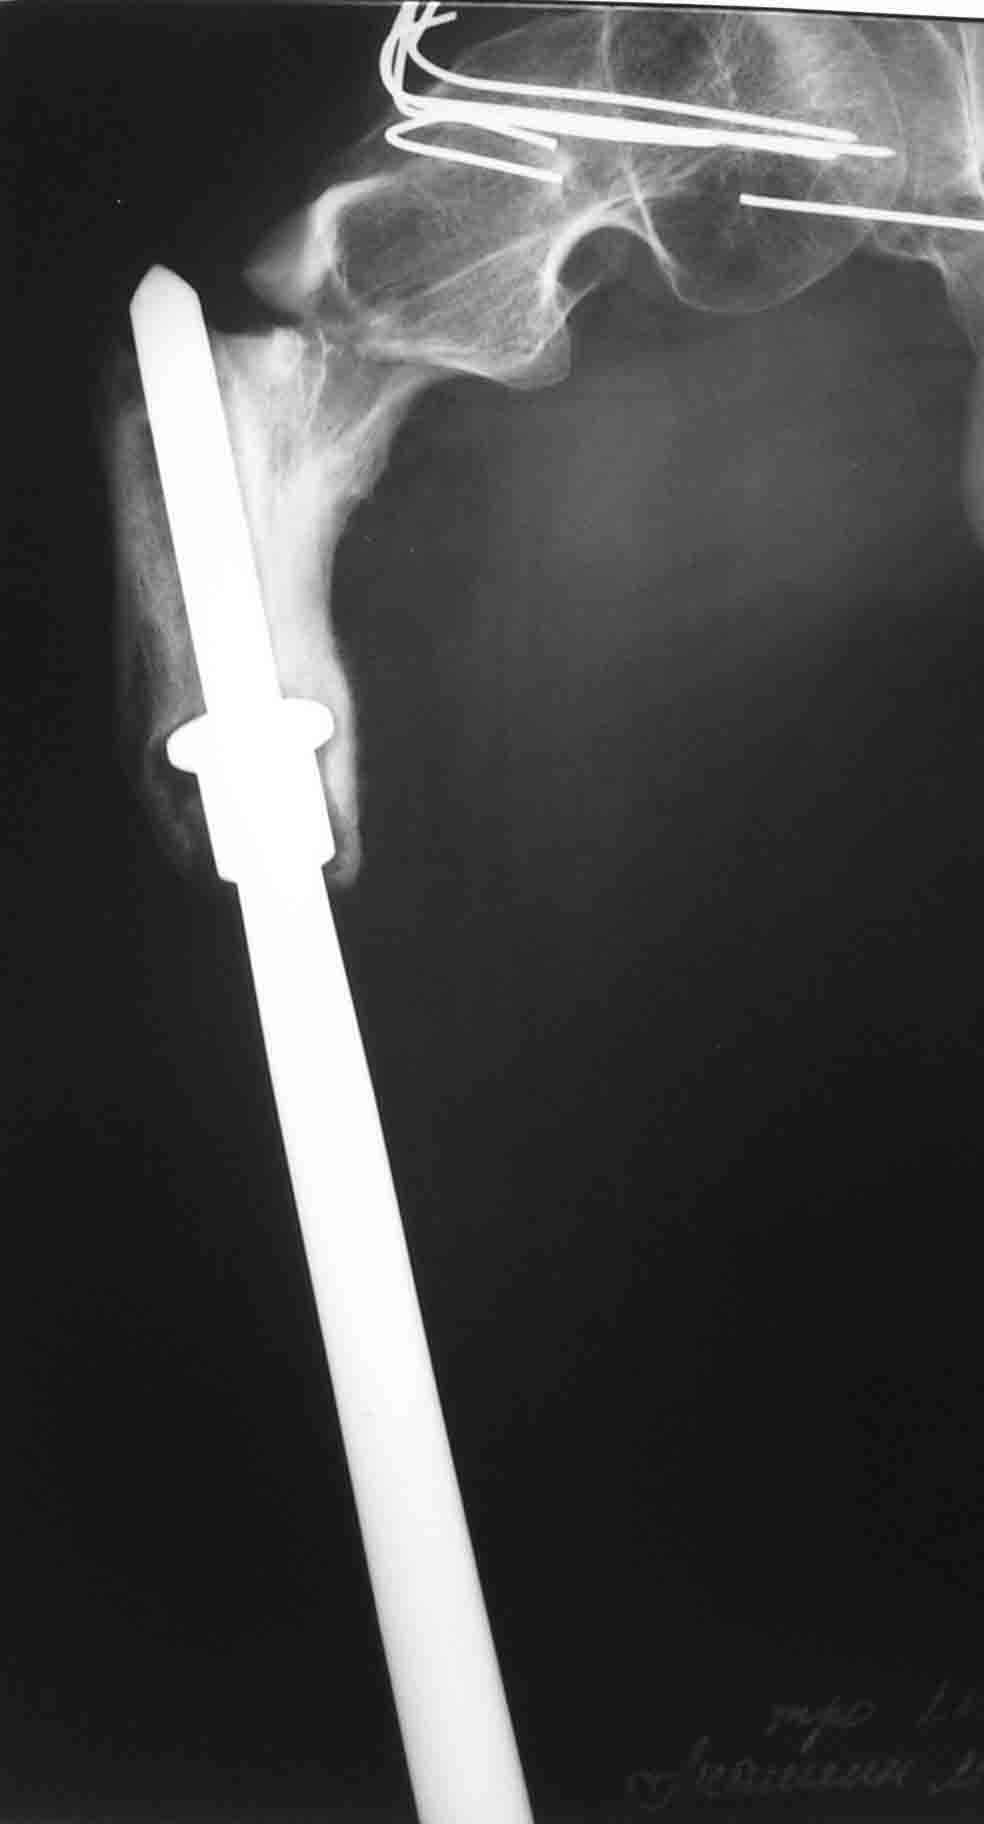

ГА> В марте этого года- повторный подвертельный перелом (см RG).

ГА> В настоящее время в коксите. Что дальше?

До травмы передвигался самостоятельно с дополнительной опорой (трость). Имеется укорочение ноги 15 см.

I would re-iterate suggestion for a fixed angle cable plate with cortical allograft struts around the prosthetic femur. Zimmer (and others) make them. The cables get purchase to the shaft by 1) go through horizontal slots in the plate or 2) onto grooves in the plate. The struts would be fixed by the cables too and keep the metal cables physically away from the metal prosthesis to minimize galvanic or fretting corrosion.

Impressive that he has functioned so long with a prosthetic femur shaft and knee joint. What is the etiology of the shortness? Acute at the time of resection or lack of growth or other?